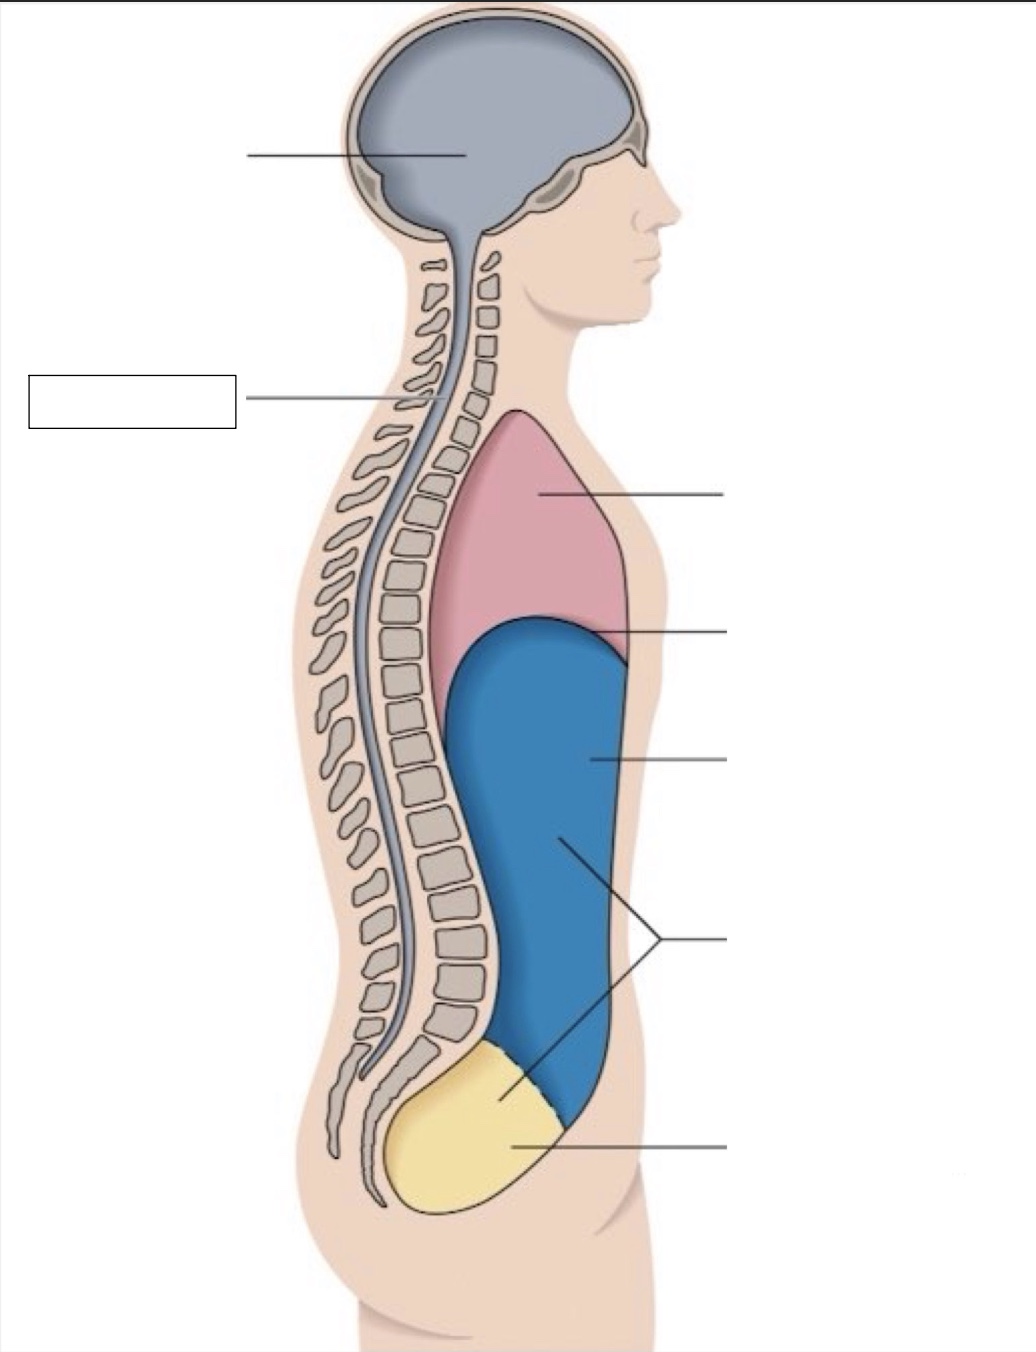

thoracic cavity

diaphragm

abdominal cavity

abdomino-pelvic cavity

pelvic cavity

spinal cavity

cranial cavity